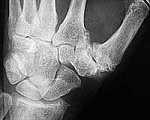

- Bild mit Bildunterschrift

- Durch Rheuma geschädigte Hand

Durch die Zytokine, die die Immunzellen ausschütten, wird die Gelenkhaut stark geschädigt. Ergüsse bilden sich, die in das Gelenk hineinwuchern, ganz ähnlich wie ein Tumor. Durch die Wucherung werden nach und nach Knorpel, Knochen und Halteapparat des betroffenen Gelenks zerstört. Die Deformierung der Gelenke bringt eine schmerzhafte Bewegungseinschränkung mit sich. Am Ende versteifen sich die Gelenke oft völlig.